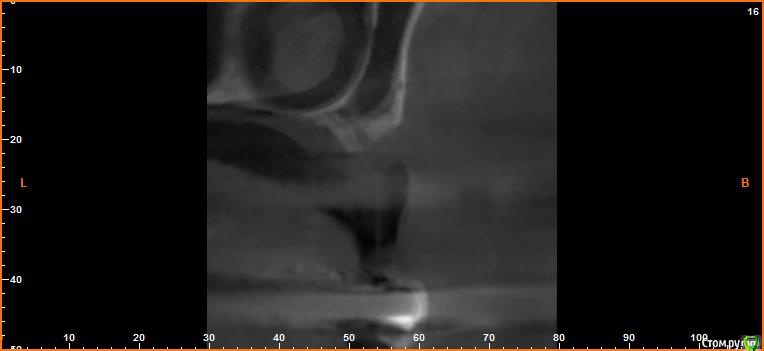

борисович Опубликовано 16 февраля, 2017 Автор Поделиться Опубликовано 16 февраля, 2017 Если сделать только синус получиться поставить импланты только в проекции 16,17 . В проекции 14,15 строение гайморовой пазухи узкое очень, вы думаете не стоит заниматься вертикалью? Спасибо за ответ Ссылка на комментарий